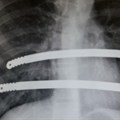

Workshop emphasises benefits of Nuss procedure for sunken chest deformity